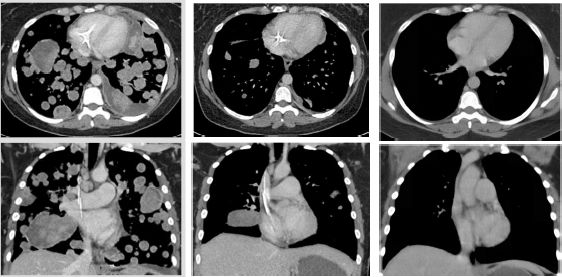

我们可以清楚的看到,这位极晚期的肉瘤患者,肿瘤已经快要填满双肺,经过LOXO-101治疗12周期,肿瘤几乎完全消失!

治疗前 治疗3周期第1天 治疗13周期第1天